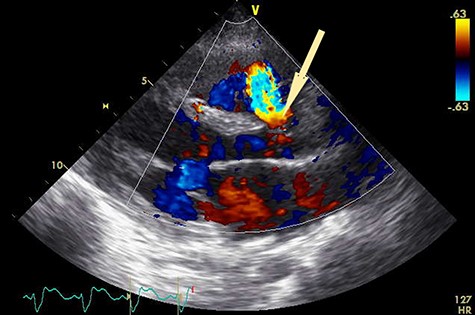

An electrocardiogram showed sinus tachycardia and ST depression in leads V4-V6. A chest X-ray revealed severe lung congestion and cardiomegaly. Transthoracic echocardiography (TTE) showed a ruptured SVA connecting to the right ventricle (RV), a subarterial VSD measuring 10 × 12 mm, with a left ventricular ejection fraction of 47% and normal valve function with mild tricuspid regurgitation (Fig. 1). No clot or vegetation was observed. Blood tests revealed a white blood cell count of 31 000/L, serum creatinine of 321 μmol/L, aspartate aminotransferase of 5199 U/L and alanine aminotransferase of 3458 U/L. The patient was diagnosed with ruptured SVA with VSD in cardiogenic shock and transferred to our hospital for further management.

Preoperative transthoracic echocardiogram. Shunt flow (arrow) from aorta to RV.